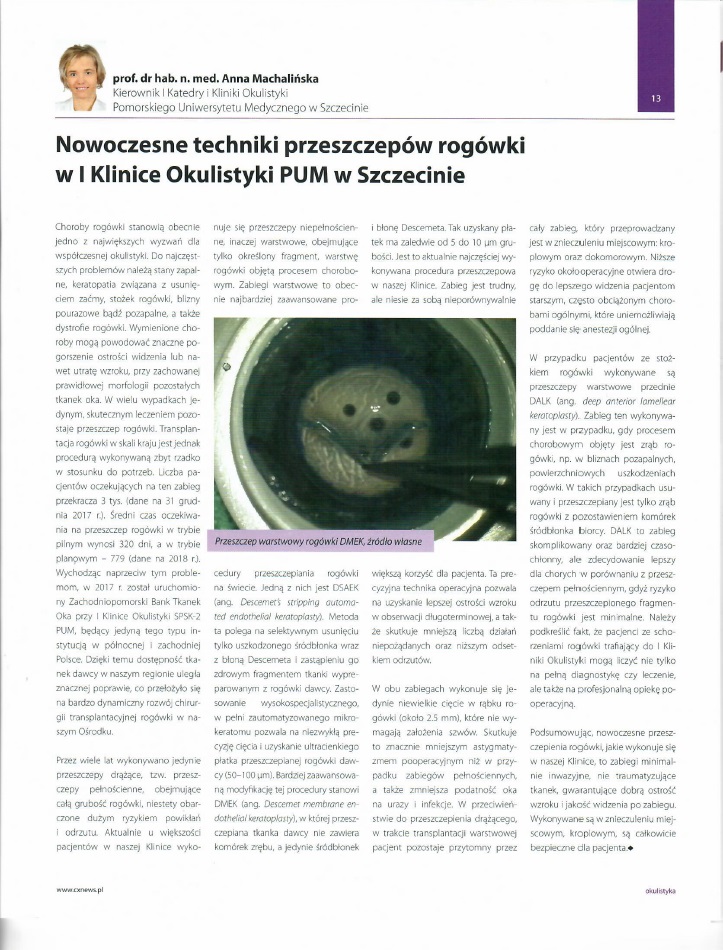

Podsumowanie roku 2023 w I Katedrze i Klinice Okulistyki

2024-01-17Szanowni Państwo!

Rok 2023 był dla naszej Kliniki bardzo pracowity zarówno w zakresie działalności leczniczej, jak i naukowej.

- Wykonaliśmy między innymi:

- 123 operacje przeszczepienia rogówki, w tym aż 95 wysokospecjalistyczne przeszczepienia warstwowe

- 2536 zabiegów usunięcia zaćmy

- 3611 iniekcji doszklistkowych w programie lekowym AMD i 854 w programie DME

- 403 zabiegi witrektomii

- 120 operacji p/jaskrowych

- Zorganizowaliśmy trzecią edycję międzynarodowej konferencji Nowe Trendy w Okulistyce Praktycznej, podczas której mieliśmy przyjemność gościć wielu znakomitych wykładowców zarówno z Polski, jak i z zagranicy, a liczba uczestników przekroczyła 300 osób!

- Opublikowaliśmy 6 prac naukowych w recenzowanych czasopismach o zasięgu międzynarodowym, o łącznym współczynniku Impact Factor wynoszącym 24,20 punktów.

- Otrzymaliśmy grant Agencji Badań Medycznych o wysokości 1 477 200 zł na realizację zadania pt. „Pionierska weryfikacja zastosowania immunomodulującego działania podprogowej laseroterapii mikropulsowej w zwyrodnieniu barwnikowym siatkówki z próbą optymalizacji protokołów laserowania 577 nm i 810 nm”

- Nasze lekarki, dr n. med. i n. o zdr. Elżbieta Krytkowska i dr n. med. i n. o zdr. Marta Wiącek, obroniły prace doktorskie z wyróżnieniem cum laude.

- Dr n. med. i n. o zdr. Agnieszka Kuligowska otrzymała główną nagrodę w konkursie na najlepszą pracę badawczą prezentowaną podczas międzynarodowej konferencji naukowej „5th Baltic Sea Eye Conference” w Rostocku w Niemczech.

- Prof. dr hab. n. med. Anna Machalińska otrzymała nagrodę nagrodę Ministra Zdrowia za znaczące osiągnięcia w zakresie działalności wdrożeniowej

- Dr n. med. i n. o zdr. Marta Wiącek otrzymała nagrodę główną przyznaną przez Prezydenta Miasta Szczecin za pracę doktorską

- Poprowadziliśmy pierwszą edycję kursu z zakresu chorób powierzchni oka i podstaw keratoplastyki dla lekarzy w trakcie specjalizacji z okulistyki, a także szkolenie z zakresu mikroskopii konfokalnej dla okulistów z całej Polski.

W nadchodzącym 2024 roku nie zwalniamy tempa!

Prof. Machalińska Lekarzem Roku 2022

2022-11-25Prof. dr hab. n. med. Anna Machalińska uzyskała tytuł LEKARZA ROKU przyznany przez Kapitułę Plebiscytu Medycznego Hipokrates 2022, organizowanego przez redakcję Głosu Szczecińskiego i Głosu Koszalińskiego. Pani Profesor zorganizowała wiodące w Polsce centrum kliniczne przeszczepień rogówki, w którym przeprowadza zabiegi z zastosowaniem najnowocześniejszych technik operacyjnych chirurgii mikroinwazyjnej. W roku 2018 wprowadziła do leczenia pionierską w skali kraju metodę małoinwazyjnego przeszczepienia błony Descemeta, która umożliwia odzyskanie pełnej ostrości wzroku i nie generuje powikłań obserwowanych w następstwie tradycyjnie przeprowadzanych transplantacji. Za te unikatowe dokonania została w 2022 r. doceniona w ogólnopolskim konkursie „Zdrowa Przyszłość - Inspiracje" w kategorii „Innowacje w szpitalu - medycyna - nowatorskie metody leczenia".